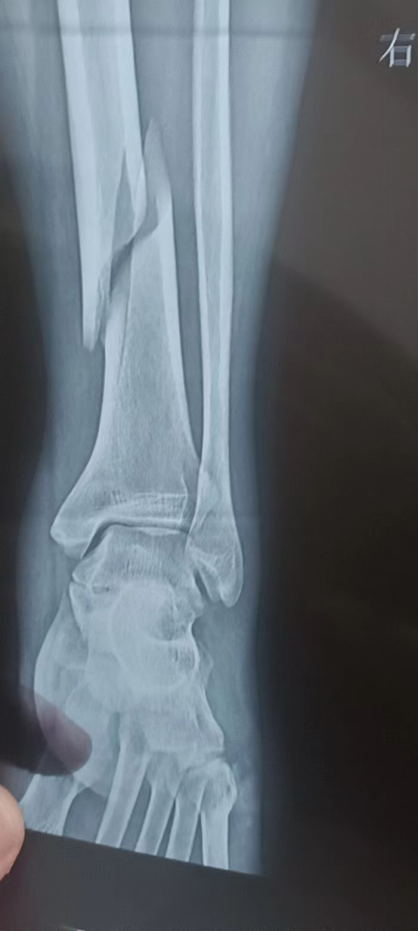

据了解,该男性患者在行走时不慎摔倒致右下肢疼痛伴有明显的活动受限,急忙到上石桥分院门诊就诊。检查提示其右胫骨骨中下段骨折。患者及家属要求由上级医院专家指导下进行手术治疗,遂汇报至商城县医健集团。集团在了解情况后,决定派我院骨二科李方辉副主任医师去上石桥分院指导开展手术。

在综合考虑患者的身体状况与患者本人意愿后,决定为患者实施手术治疗。在李方辉副主任指导下,该患者于2月8日下午17:02在腰椎麻醉下行右胫骨骨折切开复位内固定术,手术过程十分顺利,术中已解剖复位。术后复查提示骨折端已复位,对位对线良好,内固定稳定,患者对手术效果非常满意。